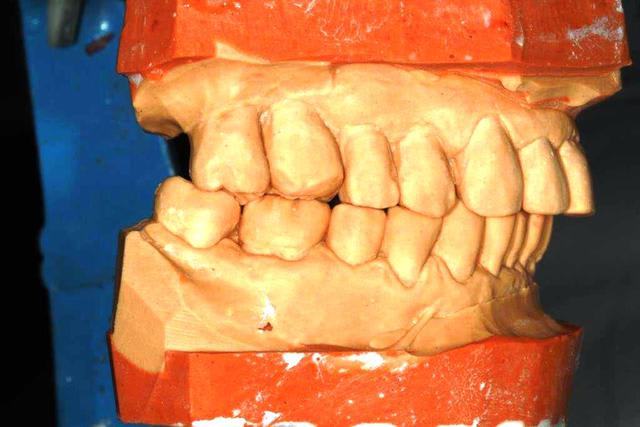

revue la patiente ce jour...avec un joli scan...rien de réjouissant.

Néanmoins, le plan de travail se met en place, et aujourd'hui, détartrage (irrigation à la betadine) constat que le terrain est miné, mais je vais quand même jouer la conservation.

Empreintes pour préparer un Waxup

les conseils sont les bienvenus, bien sur

Pourquoi conserver? parce que je crois que c'est la bonne voie

Ensuite si la situation se dégrade, il sera toujours temps de pratiquer les avulsions